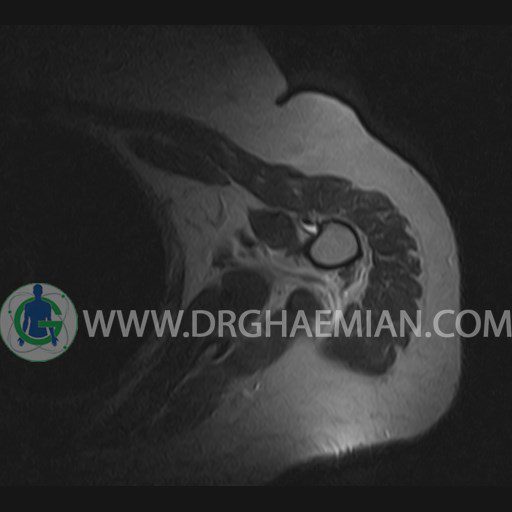

ام آر آی آتروفی عضلانی کتف بیمار

ام ار آی کتف یک روش تصویربرداری است که به وسیله آهنرباهای قدرتمند از قسمت کتف تصاویری ایجاد می کند. این نوع تصویربرداری از تشعشعات استفاده نمی کند. در این کیس آتروفی عضلانی کتف به همراه پارگی تاندون بالاخاری، بورسیت ساب دلتوئید و افیوژن مفصل دیده می شود.

– Complete tearing of supraspinatus tendon with grade 2 retraction and muscle atrophy

– AC joint hypertrophy with subacromial – subdeltoid bursitis

– Glenohumeral joint effusion

are seen.